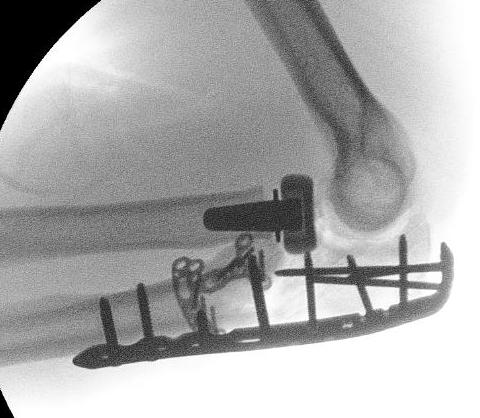

Olecranon plate + ORIF Type II coronoid process + radial head replacement

Olecranon plate with radial head replacement

Olecranon plate with radial head replacement + LCL repair

Olecranon plate + medial coronoid buttress plate + radial head replacement

Lateral Kocher approach

- +/- ORIF /replace radial head

- +/- repair / reconstruct LCL

+/- hinged fixator